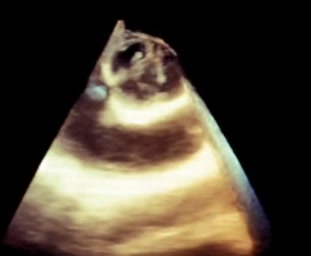

Endocardite della valvola aortica

Daniela Torta